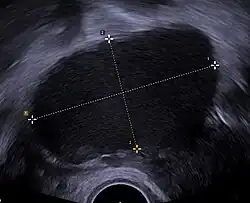

Ultrasound

Use of pelvic ultrasound may identify large endometriotic cysts (called endometriomas). However, smaller endometriosis implants cannot be visualized with ultrasound technique.[78]

Vaginal ultrasound has a clinical value in the diagnosis of endometrioma and before operating for deep endometriosis.[79] This applies to the identification of the spread of disease in women with well-established clinical suspicion of endometriosis.[79] Vaginal ultrasound is inexpensive, easily accessible, has no contraindications and requires no preparation.[79] Healthcare professionals conducting ultrasound examinations need to be experienced.[79] By extending the ultrasound assessment into the posterior and anterior pelvic compartments the sonographer is able to evaluate structural mobility and look for deep infiltrating endometriotic nodules noting the size, location and distance from the anus if applicable.[80] An improvement in sonographic detection of deep infiltrating endometriosis will not only reduce the number of diagnostic laparoscopies, it will guide management and enhance quality of life.[80]